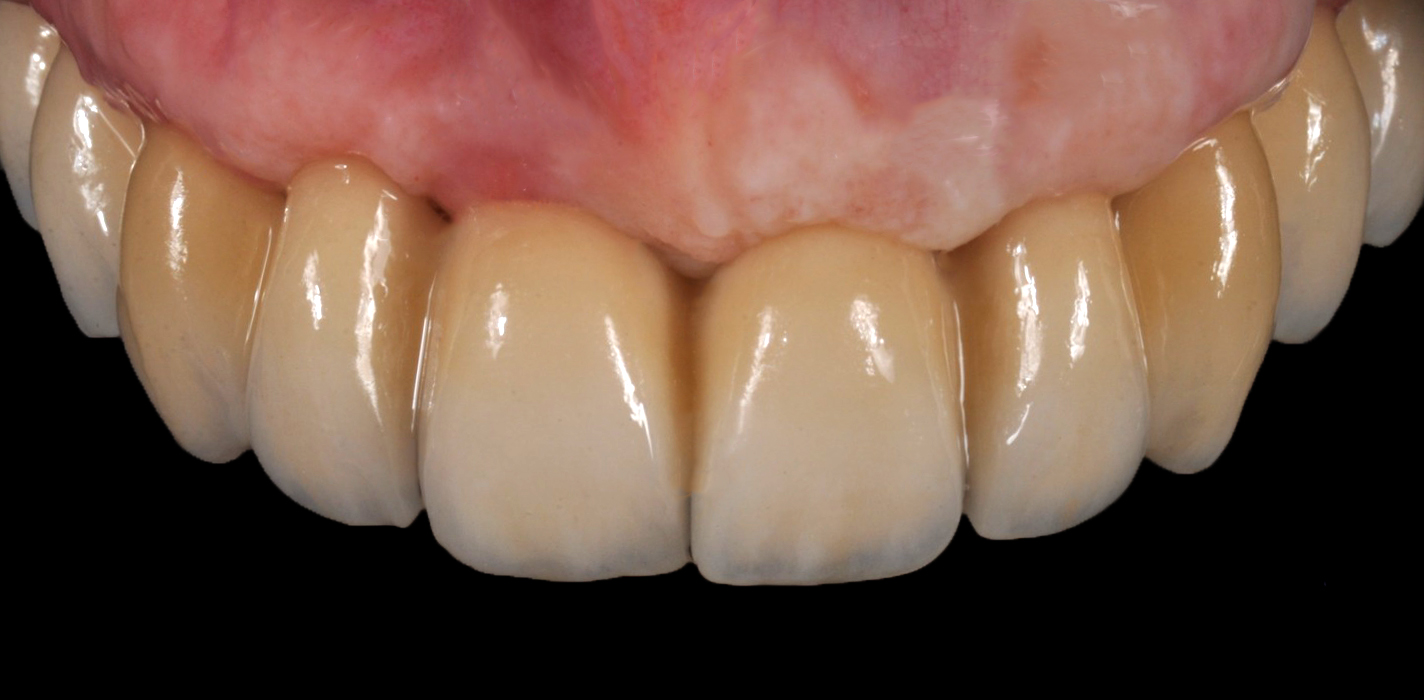

La parte di ceramizzazione è stata affidata ad una solida certezza interna al nostro laboratorio DentOne: Fabrizio Pasini, il quale ha espresso il suo sublime gusto estetico stratificando ad arte una base in CoCr con ceramica Shofu (Fig. 17, 18, 19, 20, 21).

Fig. 19. Vista vestibolare della ceramizzazione conclusa

La consegna dall'arcata definitivamente ceramizzata e con le connessioni, solo minimamente pulite dall'ossido creato dai passaggi in forno, ha generato le radiografie di validazione della corretta lavorazione, sia meccanica che estetica, permettendo al paziente di tornare alla sua frizzante vita pubblica, sfoggiando un sorriso all'altezza dello studio Imburgia di Palermo (Fig. 22, 23).

Fig. 22. Consegna dell’arcata in metallo/ ceramica